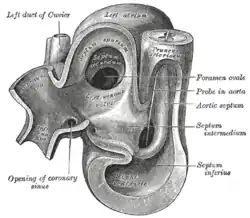

Heart of human embryo of about 35 days

Heart of human embryo of about 35 days Atrial septal defect with left-to-right shunt

During development of the baby, the interatrial septum develops to separate the left and right atria. However, a hole in the septum called the foramen ovale allows blood from the right atrium to enter the left atrium during fetal development. This opening allows blood to bypass the nonfunctional fetal lungs while the fetus obtains its oxygen from the placenta. A layer of tissue called the septum primum acts as a valve over the foramen ovale during fetal development. After birth, the pressure in the right side of the heart drops as the lungs open and begin working, causing the foramen ovale to close entirely. In about 25% of adults,[3] the foramen ovale does not entirely seal.[4] In these cases, any elevation of the pressure in the pulmonary circulatory system (due to pulmonary hypertension, temporarily while coughing, etc.) can cause the foramen ovale to remain open.